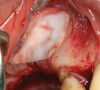

The technique described below is based on a deep buccal full-thickness flap with vertical release in the canine area, followed by creation of a “window” at the lateral wall of the sinus (Figure 2). The bony window is either removed or rotated medially with the sinus membrane and pushed inward. The Schneiderian membrane is then separated from the bone anteriorly, posteriorly, and medially until clinically sufficient space is established (Figure 3). The created space, which occupies the lower third of the sinus, is filled with a bone graft (Figure 4), and the lateral access window is covered with a collagen membrane (Figure 5).

Fig 4. Space is created between the Schneiderian membrane and the sinus walls filled with particulate xenograft.

Figure 4

Fig 5. Window is covered with a collagen membrane, and the flap is sutured back into place.

Figure 5